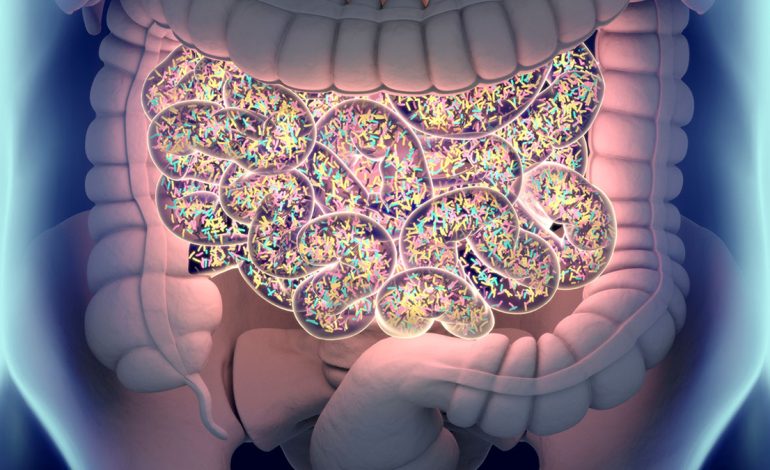

Dhimbje stomaku

Ka kaq shumë arsye përse mund të jeni duke përjetuar dhimbje stomaku sa mund të mos e lidhni fare me depresionin, por edhe ai është një shkak. Ekspertët thonë se ka një lidhje domethënëse mes trurit dhe zorrëve, që do të thotë depresioni dhe ankthi mund të jenë fajtor për dhimbjet e stomakut.

Sipas Universitetit të Harvardit, truri ka një efekt të drejtpërdrejtë në stomak dhe mund të shkaktojë dhimbje fare lehtë po ashtu edhe anasjelltas.